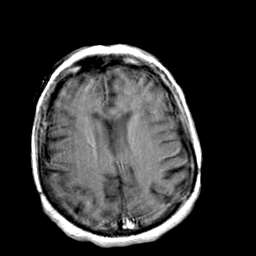

Creutzfeld-Jakob disease: gadolinium enchanced T1-Weighted MR -- Slice #16

[Home][Help][Clinical] Slice 16